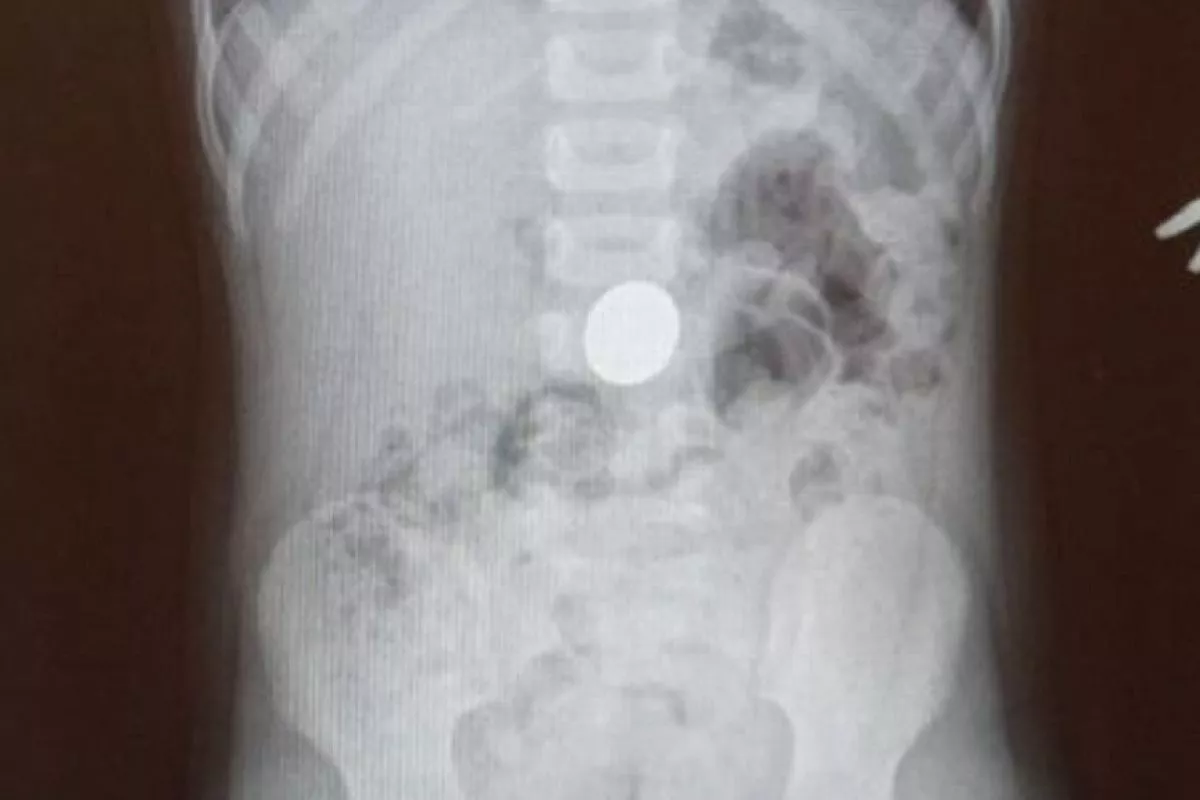

Четырехлетний мальчик поступил в приемное отделение Туапсинской центральной больницы №1 с подозрением на инородное тело в желудочно-кишечном тракте. Рентгенография подтвердила, что ребенок проглотил пятирублевую монету.

- Мальчик поступил вечером, его положили в хирургическое отделение. Контрольный снимок рентгена, сделанный утром показал, что монета осталась на прежнем месте. Было принято решение извлекать безоперационным способом. Была проведена лечебная гастроскопия под эндотрахеальным наркозом, - цитируют «Туапсинские вести» врача-эндоскописта Гора Саакяна. - Монету извлекли, ребенок уже выписан - состояние его здоровья удовлетворительное.